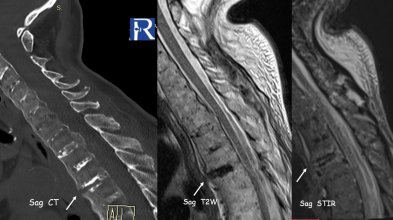

Clinical Background A 77-year-old patient with Ankylosing Spondylitis presented after a low-energy fall with acute thoracic pain. Imaging Findin ...